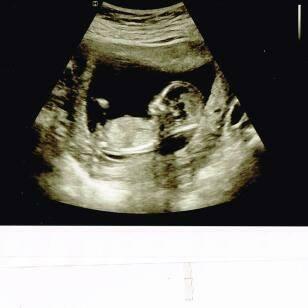

Any guesses based on NT scan?

Anyone good at the nub theory? sorry if its not a good picture. Image Attachment(s):

they say pointed up (which it looks like) is a boy . mine looks straight so im guessing girl lets see in a few weeks!

Yea I was thinking boy too because its pointing up. We will see :)

His/her private. At least I think thats what it is. I guess it could be part of the leg also, I dunno lol

You can't see anything in this sono. You're seeing the baby's leg.